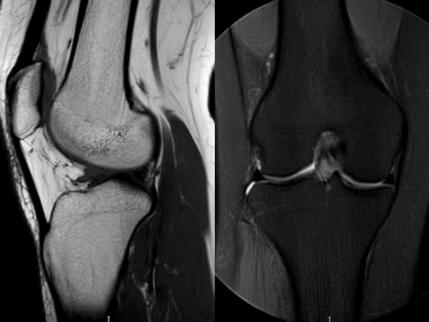

3. 上下樓“針刺痛”——軟骨的“磨砂紙預(yù)警”

場(chǎng)景:爬樓梯時(shí)膝蓋刺痛,久坐后僵硬如“生銹齒輪”

MRI偵查:發(fā)現(xiàn)軟骨變薄、缺損(早期骨關(guān)節(jié)炎信號(hào)),趕在“路面塌方”前修復(fù)

(軟骨損傷)